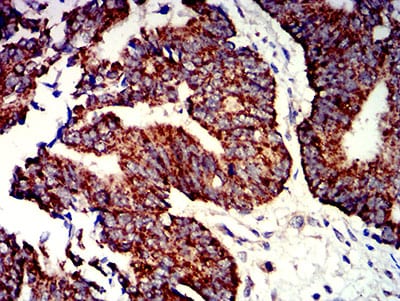

- Immunohistochemical analysis of paraffin-embedded human bladder cancer tissues using P2RY1 mouse mAb with DAB staining.

- Immunohistochemical analysis of paraffin-embedded human rectum cancer tissues using P2RY1 mouse mAb with DAB staining.